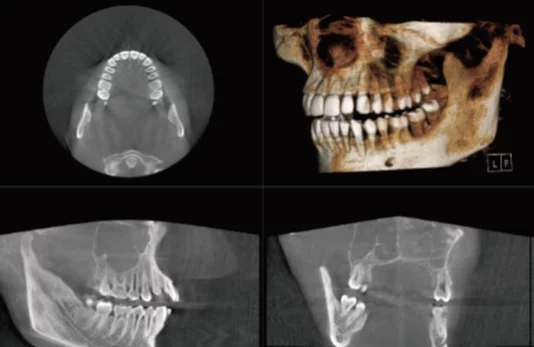

Second are the smaller FOV machines (e.g. 8 x 8 or 10 x 10). These can be an adequate dental cone beam system, as it allows capture of most of the essential anatomy. Below is a sample of a volume in this range (3D reconstruction, axial and sagittal views):

Third are the medium size FOV dental cone beam machines (e.g. 16 x 8). Below are examples of a 16 x 8 volume (3D reconstruction, axial and sagittal views):